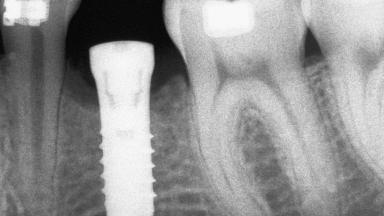

An 18-year-old man was referred for implant therapy in the posterior mandible to the Department of Oral Surgery and Stomatology (University of Bern, Switzerland). He was healthy and did not smoke. Tooth 35 was congenitally missing, involving a single-tooth edentulous space that offered an adequate mesiodistal dimension for implant placement but exhibited a typical pattern of buccal flattening. A panoramic radiograph was obtained, which revealed a sufficient vertical bone height above the mandibular canal and a normal bone structure in the edentulous area.